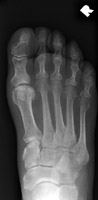

- Click on the image for a larger versionCAP radiograph of the foot shows a small fracture of the fifth proximal phalanx.